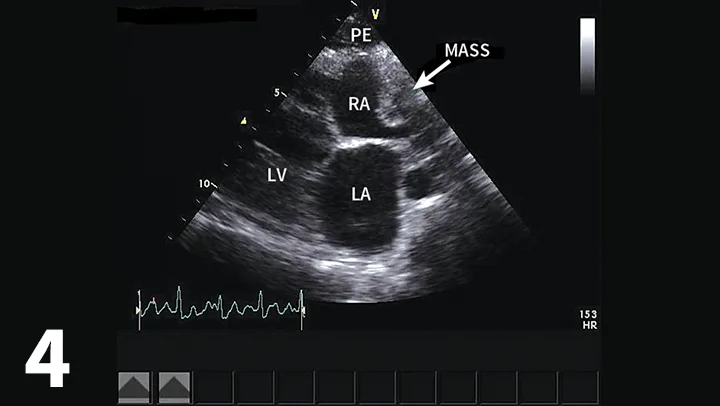

• Echocardiography confirms an echo-free space between the heart and the pericardium (Figure 1), may show cardiac tamponade (Figure 2), and may detect mass lesions.

Figure 2

Four-chamber left apical echocardiographic view showing moderate pericardial effusion with cardiac tamponade. Arrow shows diastolic collapse of the right atrium consistent with cardiac tamponade. (PE = pericardial effusion, LV = left ventricle, RV = right ventricle)

• Evaluate for the presence of cardiac tamponade (eg, diastolic collapse of the right atrium) (Figure 2).